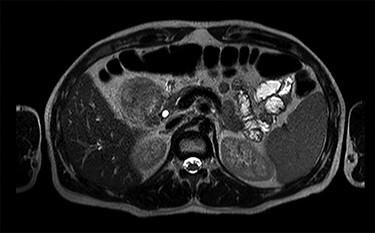

MRI scan—axial view of the large duodenal mass. Note the solid mass, enhanced by paramagnetic contrast, in the medial wall of the duodenum, invading the pancreatic head parenchyma. More proximally, in the first portion of the duodenum, there is a heterogeneous mass, non-enhanced by contrast, suggestive of an intraparietal haematoma.